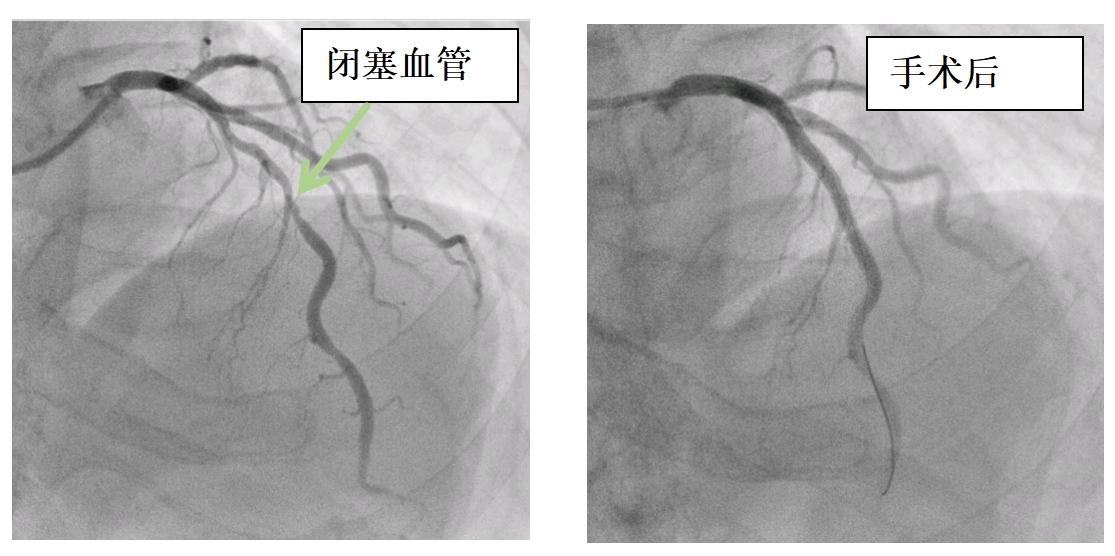

吴先生心脏前降支图像。